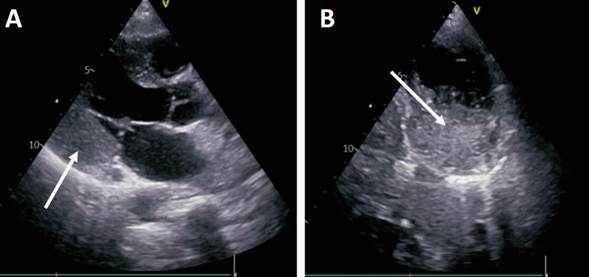

Dada la administración de potentes analgésicos que podrían enmascarar los síntomas y las nuevas alteraciones observadas en el ECG que sugieren la oclusión de un vaso epicárdico, se decide evaluar anatomía coronaria mediante cineangiocoronariografía (CACG) (figura 2). Si bien la estenosis observada sobre el ramo posterolateral podría corresponder a una disección coronaria espontánea de tipo 2a (afectación difusa del vaso con recuperación del calibre distal), los hallazgos no son concluyentes de esta entidad; no se observa, por ejemplo, tortuosidad con angulaciones próximas a 90°. Debido a la clínica (ausencia de dolor) y a lo difuso y distal de la lesión, se plantea tratamiento médico inicial y continuar evaluación en búsqueda de diagnóstico etiológico. Los ECG posteriores permanecieron incambiados. La dosificación sérica de troponinas fue negativa. Se realiza ecocardiograma transtorácico (ETT) (figura 3), que evidencia una masa probablemente intramiocárdica en región inferolateral del ventrículo izquierdo (VI).

Figura 3: Hallazgos del ETT. A) Enfoque paraesternal eje largo donde se observa masa (flecha) sobre la pared inferolateral del VI. B) Tumoración en un enfoque paraesternal eje corto, que ocupa el segmento inferior, de carácter intramiocárdico.

En cuanto al proceso diagnóstico imagenológico, el ETT es la aproximación inicial. Este permitió evidenciar la masa cardíaca y sus características, pudiendo sospechar que se trataba de un tumor cardíaco maligno localizado en la región inferolateral del VI, lo que concuerda con los hallazgos electrocardiográficos. Recordemos que los tumores malignos no están bien delimitados y suelen alterar los planos anatómicos, invadiendo y sustituyendo el tejido miocárdico nativo.